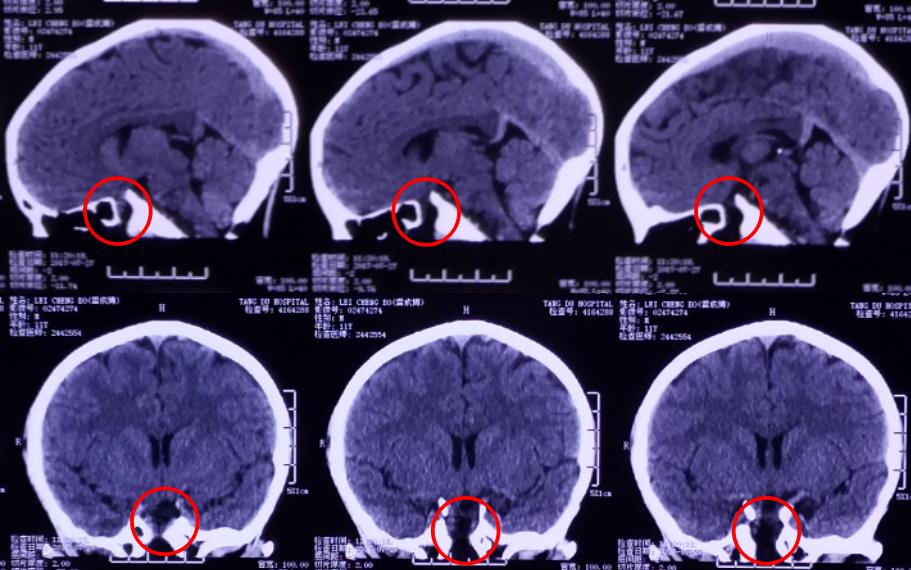

影像资料